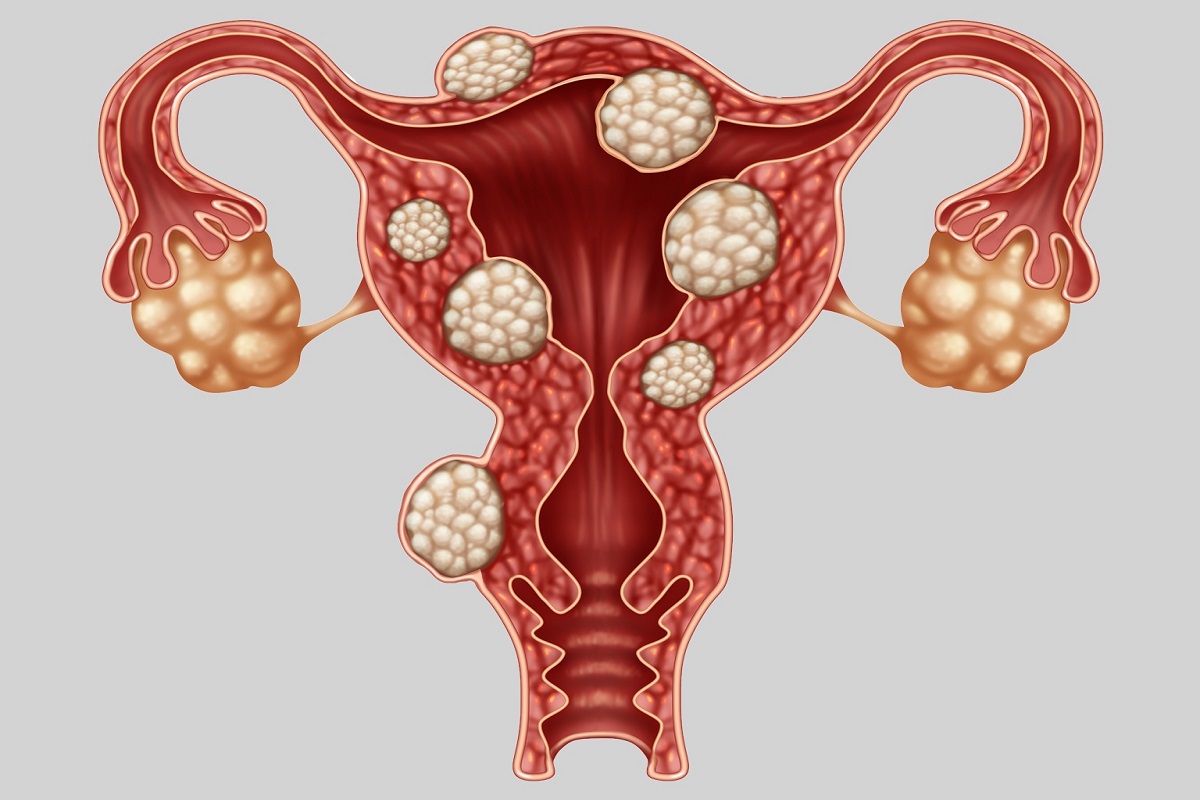

قیمت: 52٬500 تومان - دسته بندی فایل: پاورپوینتدانلود پاورپوینت آشنایی با بیماری آندومتریوز

خرید پاورپوینت حرفه ای با موضوع آشنایی با بیماری آندومتریوز با قیمت استثنایی از لوکس فایل

قیمت: 52٬500 تومان - دسته بندی فایل: پاورپوینتدانلود پاورپوینت مطالعه فیبروم رحم

خرید پاورپوینت حرفه ای با موضوع مطالعه فیبروم رحم با قیمت استثنایی از لوکس فایل